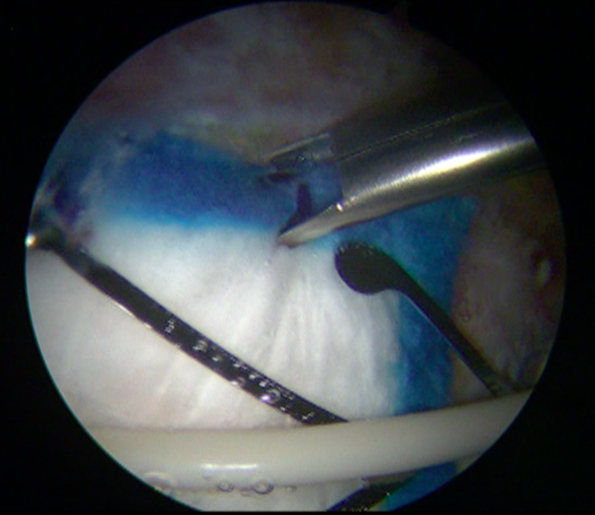

Tears are always found on the medial side, which cannot be directly observed. It is explored by palpation to rule out a complete rupture. A third portal is made at the midpoint equidistant between the PPLA and DPLA, the medium posterolateral accessory (MPLA) portal Figure 4. Through this MPLA portal, nine perforations are made in the greater trochanter at the level of the GM insertion with a 2.3mm Bioraptor® anchor drill bit (Smith & Nephew, London, United Kingdom) at a depth of 2.5cm, distributed symmetrically separated approximately 1cm from each other Figure 5. Through the DPLA portal, an 8.25mm cannula specific to the implant is inserted, and then the Regeneten® bioinductive patch loaded is passed. Once the implant has been placed in the desired position, 6 anchors of the Regeneten® system for soft tissues (4.5x6.5mm) are placed through the MPLA portal to set the patch Figure 6. Subsequently, the stability of the implant is confirmed by hip rotation and flexion-extension movements Figure 7. Instruments are removed and the skin is sutured, concluding the surgical procedure.

Figure 6 The implant is inserted through the DPLA portal and fixed with six anchors (4.5x6.5mm) through the MPLA portal when viewed from the PPLA portal.